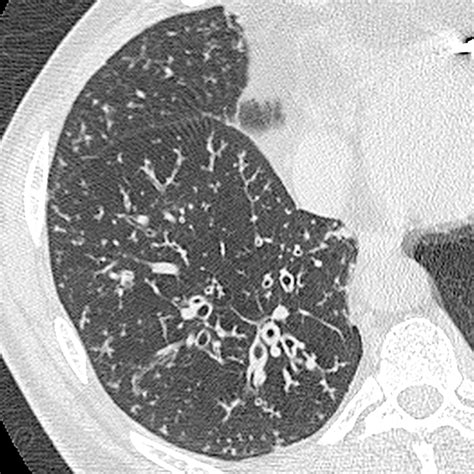

Diagnosing Bronchiolitis in Adults

Diagnosing Bronchiolitis in Adults involves a combination of physical examination, medical history, and diagnostic tests. The healthcare provider will typically:

• Conduct a physical examination to listen to the lungs for abnormal sounds such as wheezing or crackles.

• Review the patient's medical history, including any recent illnesses or exposure to respiratory infections.

• Order diagnostic tests such as chest X-rays, blood tests, and sputum cultures to identify the underlying cause of the infection.

In some cases, a pulmonary function test may be performed to assess the severity of the condition and monitor the patient's progress.